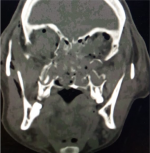

| Granulomatosis

with Polyangiitis[19] (Wegener's) |

Mean age 65-75 years | Ocular pain, diplopia, decreased visual field with sign suggestive of URTI or lung infection. | Imaging findings depend on orbital location, the extent of involvement and invasion into adjoining structures.

CT - show sinusitis and bony invasion MRI - identifies granulomas and deliniates mucoid plugs. |

Granulomatosis with Polyangiitis. Non-contrast axial CT images in soft tissue window showing left orbital large infiltrative extra- and intra-conal soft tissue masses that mould to the orbital contour associated with proptosis of the globe. Ipsilateral maxillary sinus in the same case showed pansinusitis with medial wall sclerotic thickening. | |